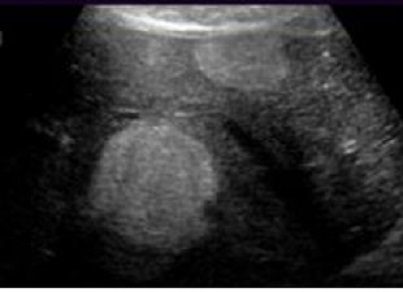

Image echographique de

hemangiome du foie , sa bord est net , lisse et

hyperechoriche situe du foie droit |

Hemangiome du foie : Image de l'absence de vascularisation

de ce tumeur sur Doppler |